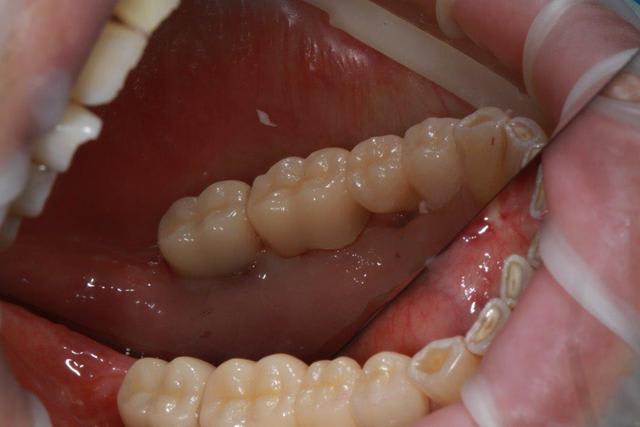

Ce matin repose d'un nouvel implant et comme je ne veux pas prendre de risque, et que les dents adjacentes doivent être couronnées, je pose un bridge en emax press, mais scellé au ciment provisoire...

Si l'implant va bien le bridge sera déposé, coupé, et 44/46 seront collées définitivement après traitement acide et silane.

Si par hasard l'implant pose problème, dépose et bridge collé.

Dépose gratuite bien sur et repose gratuite aussi, le bridge n'est pas facturé non plus, il le sera sous forme de 2 couronnes que cette fois ci l'implant fonctionne ce que j’espère, ou laissé en bridge si l'implant devait être retiré.

Le fait de scellé au ciment temporaire ne pose en principe pas de problème pour 3 à 6 mois.

mettre 3 screw-posts dans les racines de la 6 ce n'est pas du sur-traitement c'est un assassinat dentaire !

j'ai choisi la moins mauvaise solution, fonction de ce que je sais faire, 3 screws post scellées, et résine...pas top mais ça ne mérite pas la chaise électrique.

Bien sur j'aurais gagné plus en faisant un IC à clavette, comme à la mutuelle... mais pour avoir passé 1h30 et cassé 8 fraises sur le dernier IC clavette que j'ai déposé, j'évite ce genre de travail.